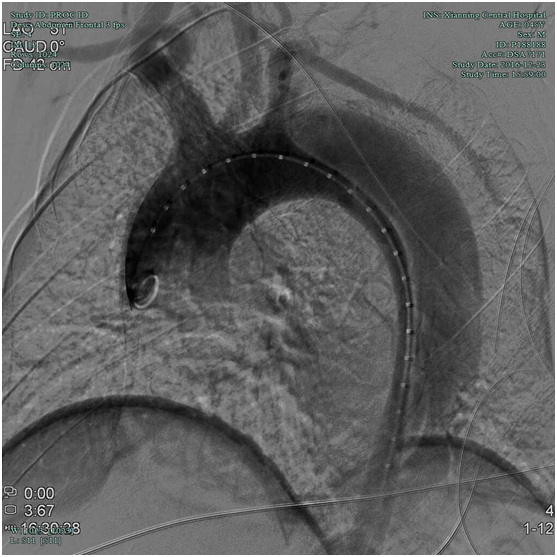

血管外科:胸腹主动脉夹层支架植入术

近日,血管外科在外请专家指导下成功行胸腹主动脉夹层覆膜支架植入术2例,其中一例患者已顺利出院,结束了我院治疗胸腹主动脉夹层需要转院的历史,血管外科将进一步发展血管外科腔内治疗技术和结合手术治疗的血管杂交技术。